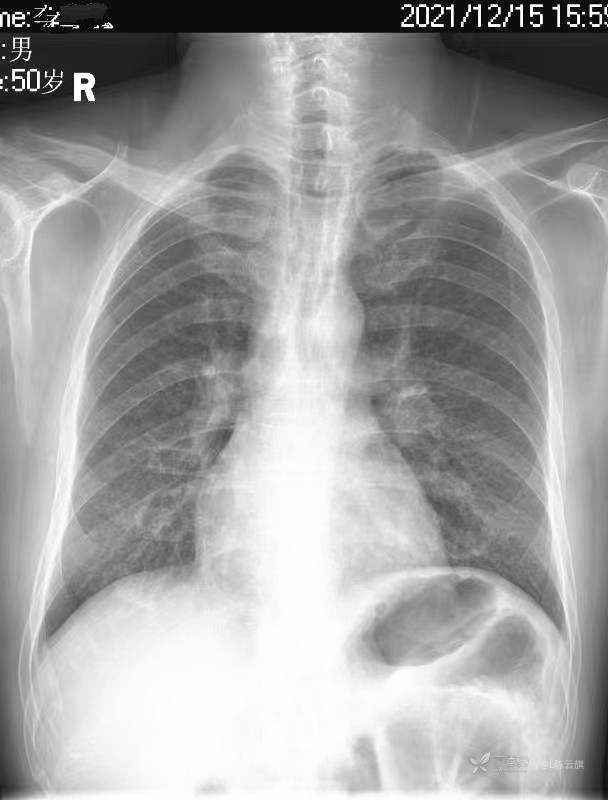

华夏览雄 达人已点赞1、患者男,51岁,精神病长期住院患者,主要病史只有时不时觉得腹部不适,其他不详。系列胸片为定期胸部检查。